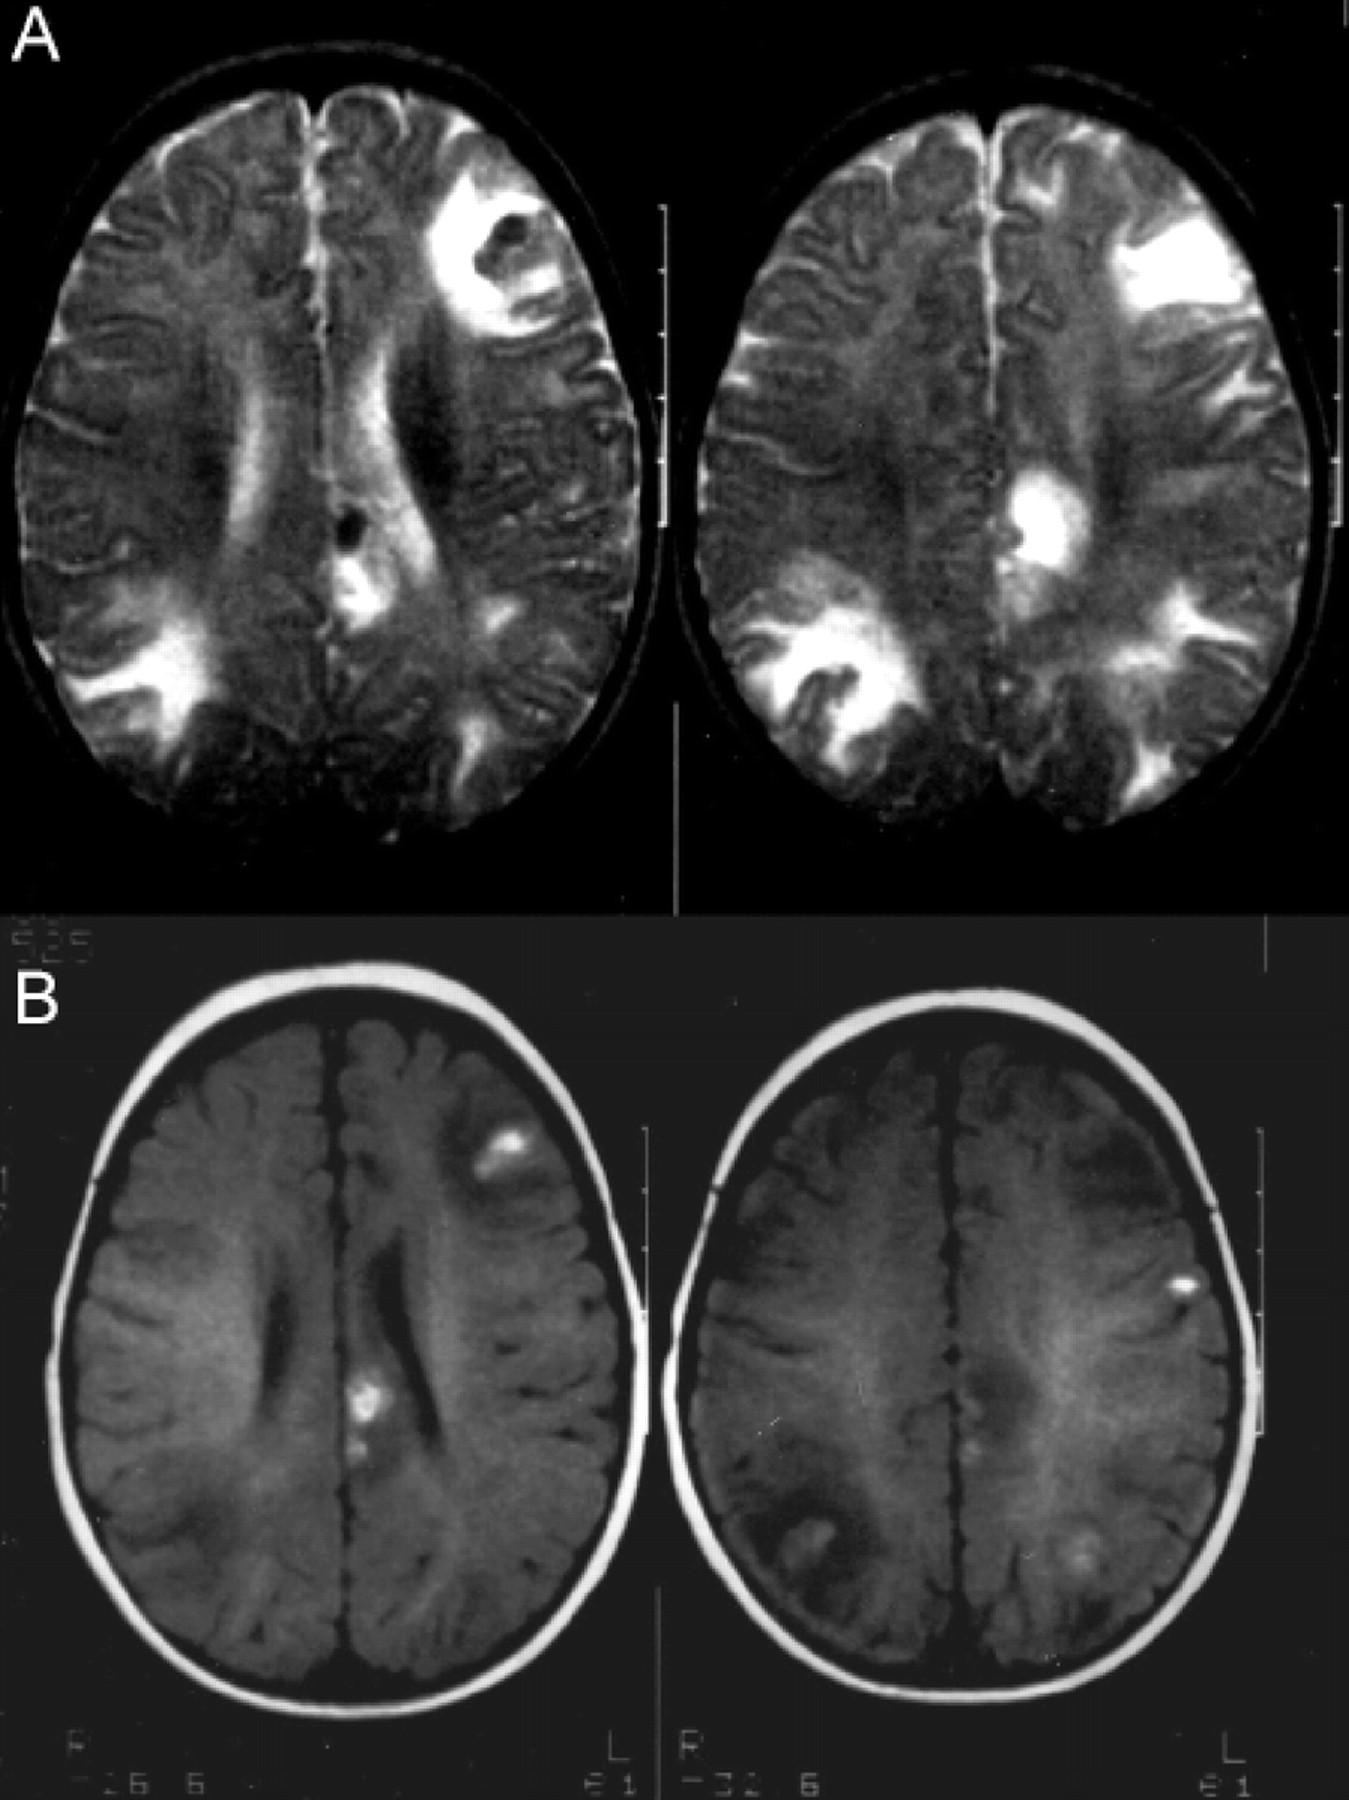

提出了四种模式的大脑参与描述ADEM的磁共振成像结果21:1)ADEM小病变(少于5毫米;图1);2)ADEM大支流,块状病变,簇状或频繁广泛perilesional水肿和质量效应(图2);3)ADEM附加对称bithalamic参与(图3);和4)急性出血性脑脊髓炎(咳咳),当一些出血的证据可以确定大脱髓鞘病变(图4)。核磁共振成像模式似乎并不与任何特定的结果或残疾,作为大型儿童群体中观察到,21因为大多数病变往往解决后续成像研究。21日,32然而,这种分类可能是有用的在考虑的鉴别诊断ADEM和可能有助于识别那些孩子来说,初始ADEM-phenotype真的是第一个女士的表现。

图1所示。急性播散性脑脊髓炎与小病灶。(一)轴向t2加权MRI显示双边、不加边hyperintense病变在中央,室旁,juxtacortical白质,(B)包括花托和内部胶囊,一个17个月大的男孩,麻疹疫苗接种后2周。